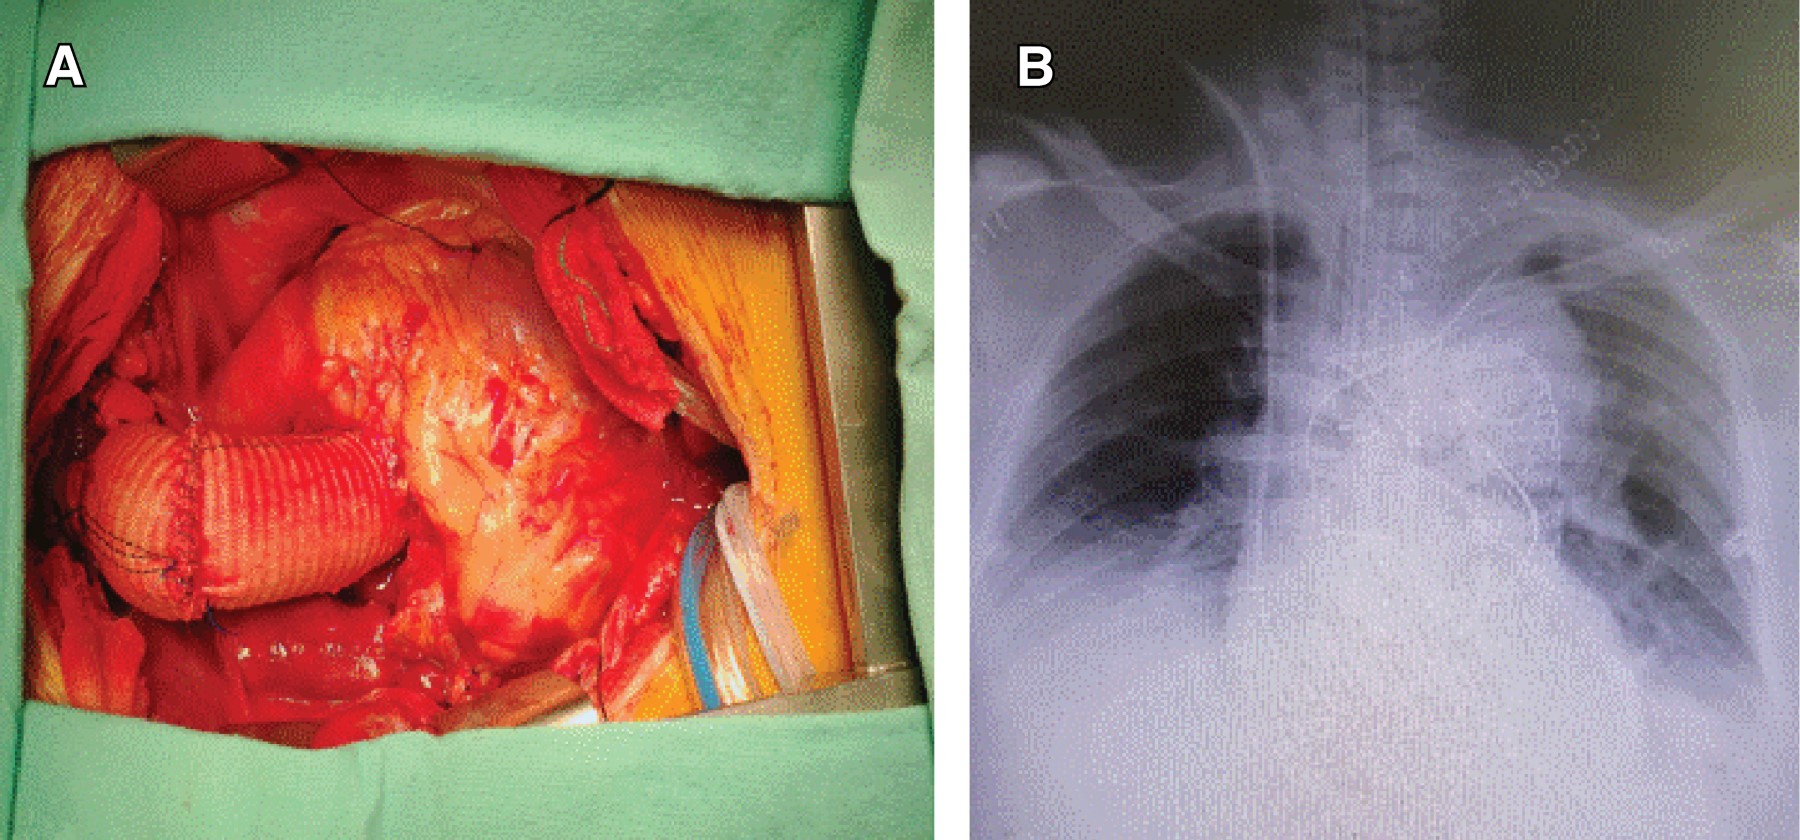

With the previous studies it was decided to undergo surgical treatment. We were provided with a 31 mm × 15 cm GORE® endoprosthesis (Figure 2A), we manually made a 32 mm woven Dacron tube with a 10 mm chimney and another tube of 10 mm for the left carotid and one of 12 mm that will serve for the brachycephalic trunk (Figure 2B). An ultrasound-guided right common femoral puncture was performed and a 6 Fr introducer was placed; a right infraclavicular incision was made, the right subclavian artery was located and vascular control performed and 5/0 purse-string tourniquet, left infraclavicular incision was made and end-to-side anastomosis is performed with a 10 mm woven Dacron tube, median sternotomy was performed and extended with left cervicotomy. Mediastinal structures were dissected, carotid sheath was also dissected, with vascular control of the carotid artery. One vascular shunt was placed, an end-to-side anastomosis performed with a 10 mm woven Dacron. Then, pericardium was incised, the edges marsupialized, a simple purse-string was placed in the right atrium and in the right upper pulmonary vein, and heparin administered, with optimal activated coagulation time, the right subclavian artery was cannulated with a 17 Fr cannula, a trilumen catheter is placed for distal perfusion in the right subclavian artery, the right atrium and right upper pulmonary vein were also cannulated. The body temperature was lowered to reach 18 oC. Then, aortic cross-clamping was performed, aortotomy and direct Custodiol as cardioplegia administered into coronary ostia. Proximal aorta was reinforced with Teflon bands and aortic valve resuspension and anastomosis of a 32 mm woven Dacron tube were performed in ascending aorta. In deep hypothermia, the centrifugal pump was stopped and selective cerebral perfusion was started with a roller pump at 800 ml per minute. Aorta was unclamped and aortic arch resection performed, a hydrophilic guidewire passed through a femoral introducer under vision with true light echocardiography, a GORE-type thoracic endoprosthesis releaser ® was directed 31 mm × 15 cm in the descending aorta, stent was released without complications (Figure 3A). Anastomosis of the endoprosthesis to a 32 mm woven Dacron tube and later to a woven tube of the proximal aorta (supracoronarian) was performed (Figure 3B). The cannula was connected to the arch chimney and the flow is restarted with a centrifugal pump, an end-to-end anastomosis performed from a 10-mm woven tube of the left common carotid to a 10-mm aortic tube. Anastomosis was subsequently performed from the brachycephalic trunk to a woven Dacron tube of 12 mm supra-aortic. Temperature rise began, at optimal temperature extracorporeal circulation is weaned, achieving it on the first attempt, in hemodynamic stability structures are decannulated and anastomosis is performed from 10 mm woven Dacron used as chimney to 10 mm woven Dacron extraanatomical that passes through the left pleura to the left subclavian artery (Figure 4A). Protamine was administered, hemostasis performed and chest draining tubes placed. Chest closure was performed as usual. Surgical procedure concluded without complications. In ICU, a chest X-ray was requested, without observing changes (Figure 4B).

Figure 4